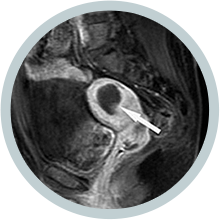

• 시술 6개월 후 시술 6개월 후

하이푸 시술 6개월 후

MRI 조영증강영상에

절제된 근종이

유의하게 축소됨